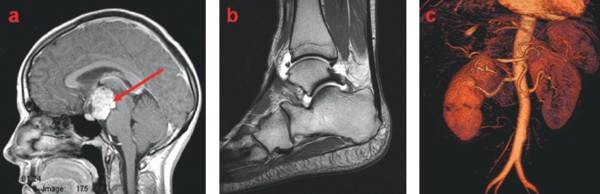

Les agents actuellement commercialisés sont caractérisés par une pharmacocinétique à distribution dite interstitielle, c’est-à-dire qu’après l’injection par voie intravasculaire, l’agent se répartit dans tout l’espace extracellulaire. Ces agents permettent notamment de détecter des tumeurs cérébrales, mammaires…, des pathologies ostéo-articulaires, et permettent de réaliser l’imagerie des vaisseaux, procédure appelée angiographie (Figure 2).